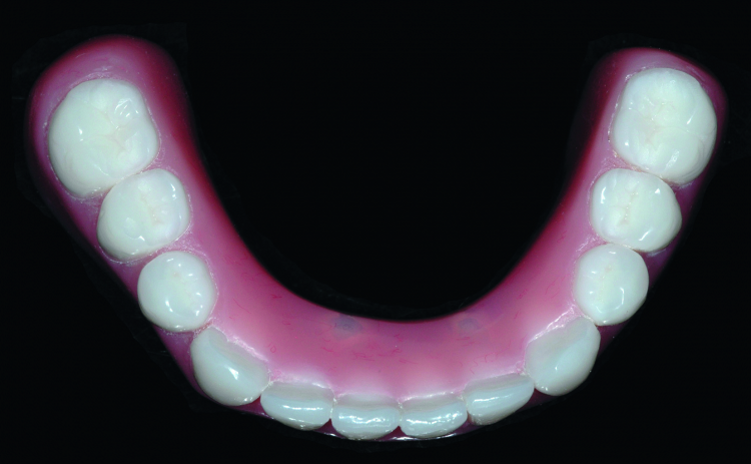

Fig. 10: Completed laboratory restoration; note the termination the arch at the first molar to avoid excessive cantilever length. The chrome frame is opaqued on the functional side to prevent gray show-through.

The denture set-up with a final bite record were returned to the dental lab, the cast metal frame was seated on the improved dental stone cast and areas around the stone copy of the SynCone caps were blocked out prior to processing. The SynCone caps will be captured intraorally, rather than having them processed in the dental laboratory. All work was completed on the duplicate stone cast rather than the original working cast. The cast metal frame was opaqued to prevent grey show-through. The set-up was transferred to the cast with the metal frame and the dentures were processed (Figs. 10 & 11).

Because the Atlantis Conus concept results in a fully implant-supported prosthesis, the peripheral borders of the finished structure were greatly reduced and the occlusal table was abbreviated at the first molar. The length of functional arch follows the identical AP spread principles used for hybrid prosthetics to avoid excessively long cantilevers.